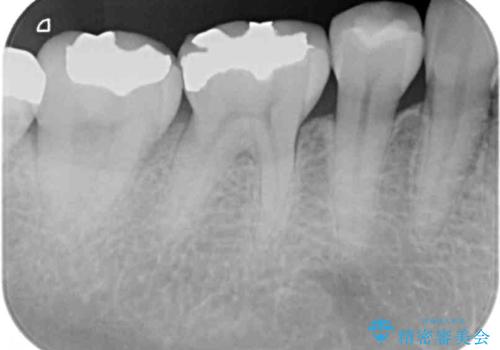

- 口を開けたときに目立ってしまう銀歯をセラミックに替えたいとのことで来院された患者様です。

上顎や親知らずにも銀歯がありましたが、今回の治療では目立つ下顎の銀歯4歯をセラミッククラウンやセラミックインレーに置き換えることにしました。